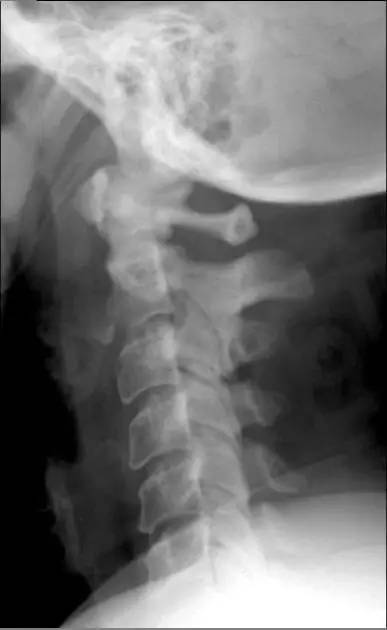

4. Clay-shoveler 骨折

铲土者骨折,是发生在低位颈椎或高位胸椎棘突(C7 或 T1 最多见)的一种撕脱骨折。损伤是由于工人企图向上扔一满铁铲的泥土,但是泥土粘住铁铲,引起一个突然的屈曲力量反作用于颈部引起的损伤,故命名。

图为铲土者骨折(C3~C5)的平片(A)及 CT 扫描(B)(来源:Radiopaedia)